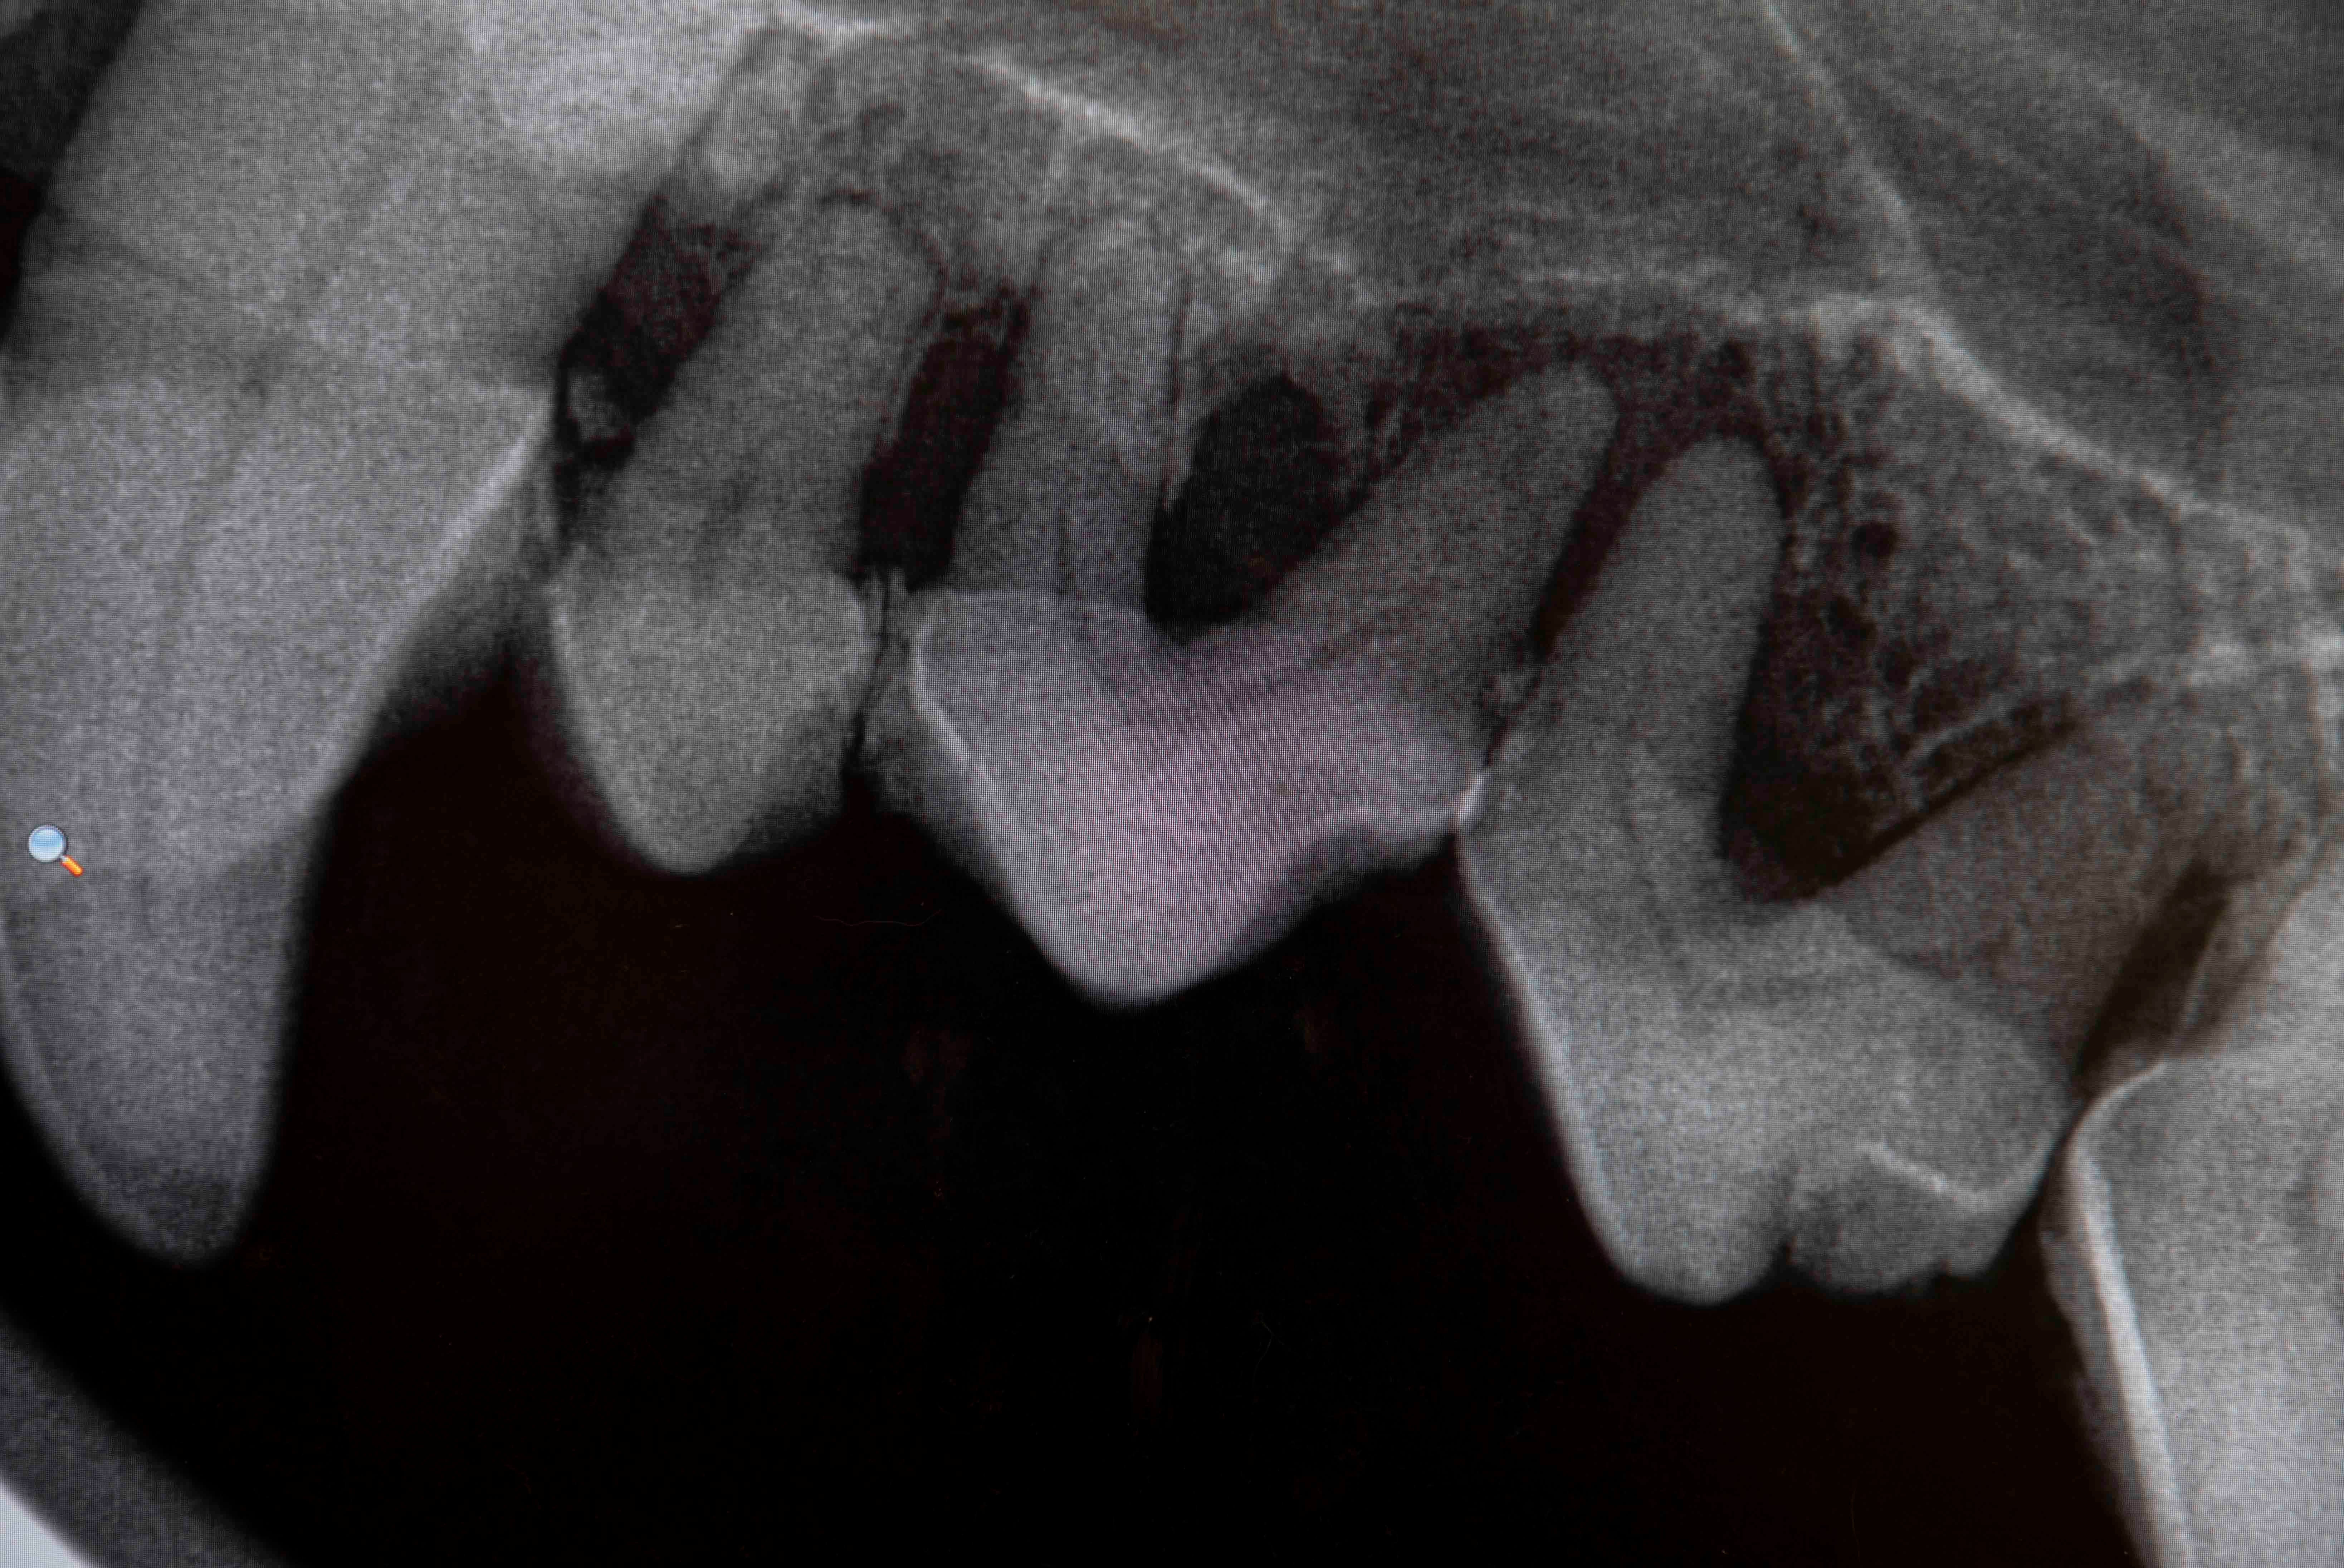

Digital Radiology

Advanced Dentistry